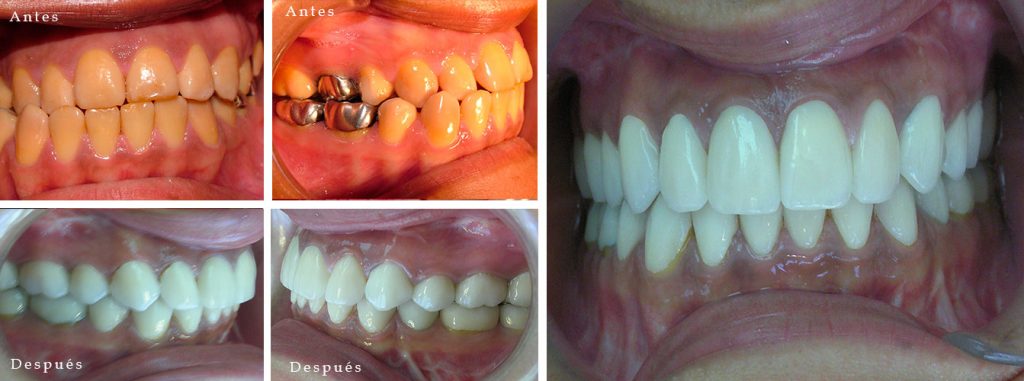

Paciente con progenie, asimetria esqueletal y piezas dentarias con falta de la capa de esmalte.Tratamiento: Ortodoncia, Cirugía y Rehabilitación. (V. Barra)